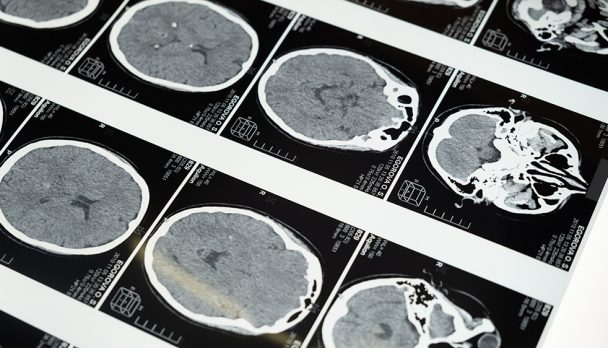

We often hear about “dementia breakthroughs” in the news – new genes being discovered, new blood tests being developed, new drugs being tested. However, there remains no effective or accessible cure for dementia.